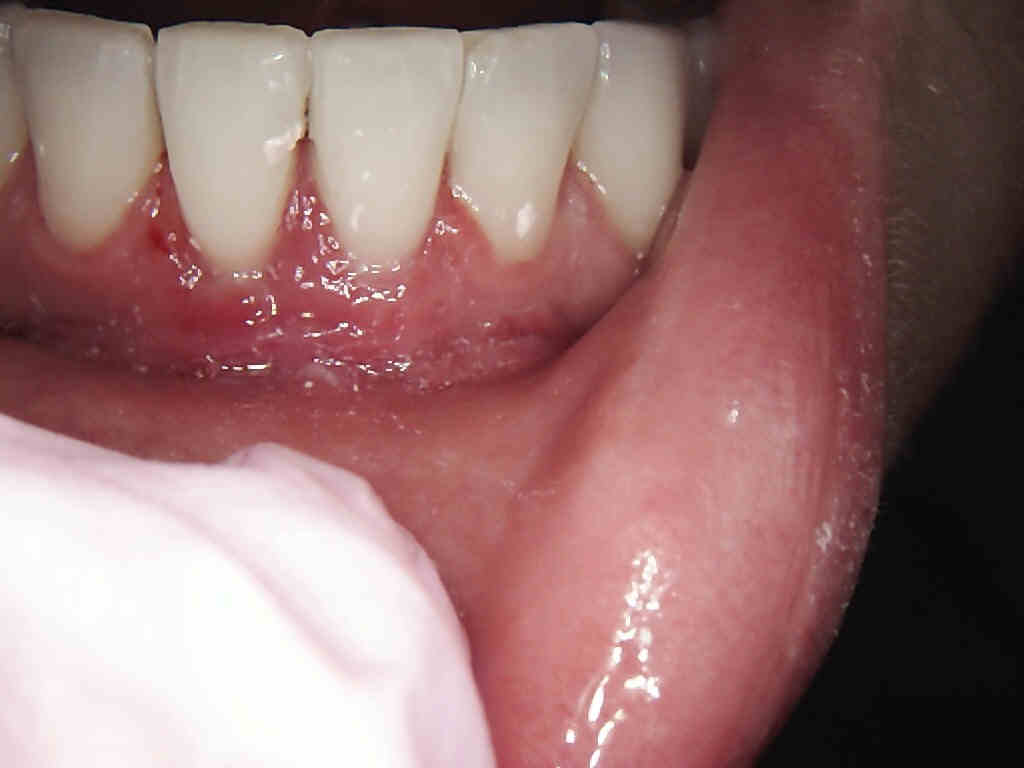

Bleeding Gums

Before

After

Note that these are preoperative recession cases that have minimal connective tissue.

The reason for the connective tissue graft is to ensure that the patient preserves bone and minimizes horizontal bone loss.